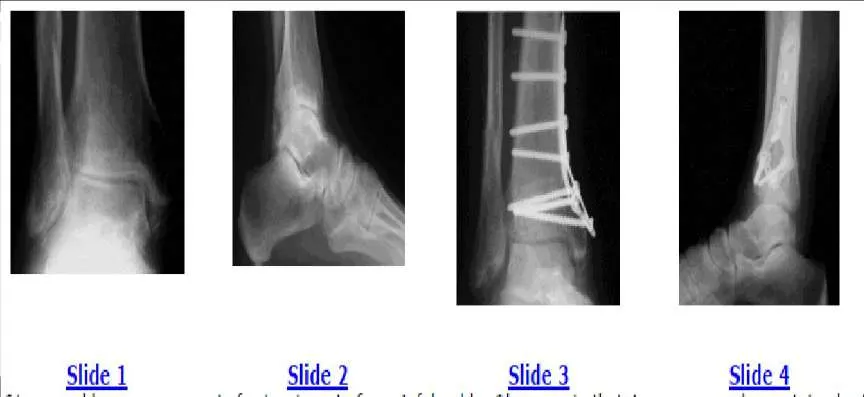

Question 10:

A 61-year-old woman presents for treatment of a painful ankle. She reports that 4 years ago, she sustained a fracture of her ankle that was treated with cast immobilization. She has experienced progressively worsening pain over the past 2 years. On examination, she has good range of motion of the ankle with crepitus and pain. Radiographs are presented (Slide 1 and Slide 2). All of the following are acceptable forms of surgical correction except:

Options:

- Supramalleolar osteotomy of the tibia

- Ankle arthroscopy

- Ankle arthrodesis

- Total ankle replacement

- Distraction lengthening osteotomy of the fibula

Correct Answer: Ankle arthroscopy

Explanation:

Each of the alternatives presented is reasonable except for ankle arthroscopy because it has a limited role in the management of posttraumatic arthritis of the ankle. In this patient, there is a possibility to salvage the ankle before arthrodesis or joint replacement with an osteotomy of the tibia and or the fibula. Both have a definite role in management of ankle deformity and arthritis. A closing wedge osteotomy of the tibia was performed in this patient, and she remains asymptomatic 4 years later (Slide 3 and Slide 4).